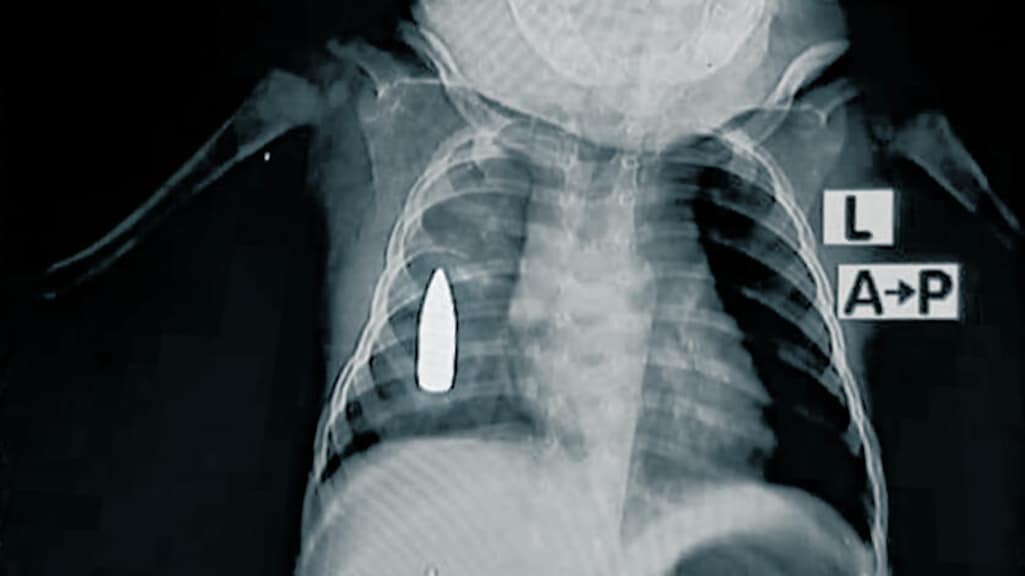

Artsen zonder Grenzen heeft röntgenfoto’s verspreid uit een ziekenhuis in een van de conflictgebieden in Soedan, waar al bijna twee jaar een burgeroorlog woedt. De beelden laten op huiveringwekkende manier zien hoe kinderen slachtoffer worden van het conflict.